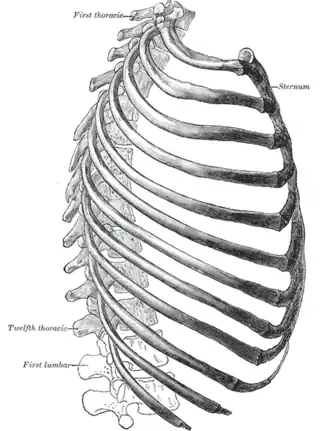

The thorax from the right. | |